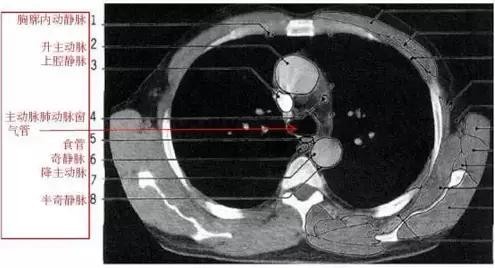

胸部的CT是通过X线计算机体层摄影(CT)对胸部进行检查的一种方法。正常胸部CT层面较多,每一层面结构所表现的图像不同。下面是胸部CT图文示意图,可帮助临床医生详细了解CT结构。我们一起来看一下吧。